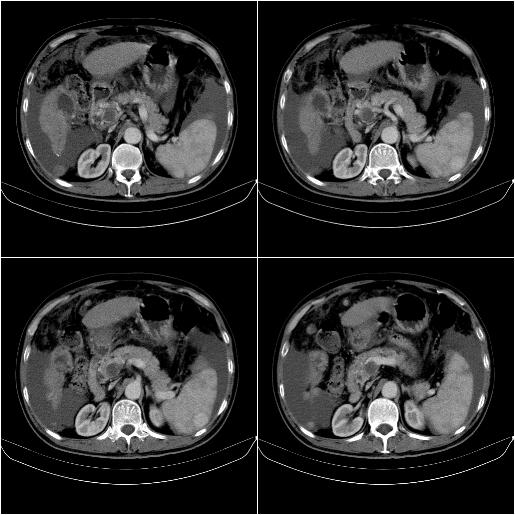

标题: CT21651:M,67Y,肝癌9月,介入术后3月。

m,67y,肝癌9月,介入术后3月。现腹胀、纳差、腹泻。

1)肝癌介入治疗术后碘油沉积不良。2)门静脉瘤栓形成,腹膜广泛性转移。3)肝硬化,脾大,腹水。4)慢性胆囊炎。